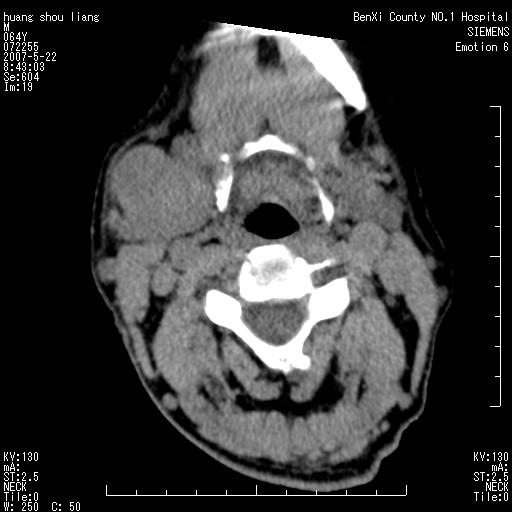

男性,64岁。颈部包块8年。最近增大。

对不起大家,可能是片子发太多有点乱,正常腮腺在下颌角的外侧,颌下腺在下颌体的中部内侧,本例在下颌角内侧偏下,和腺体一点关系都没有,从vrt和mpr上可以很明显看出来,再者肿块是好多粘连在一块的,大家在仔细看看,左侧可能也是吧,我还是考虑为肿大的淋巴结融合在一块,但性质??????

右侧腮腺下部均匀软组织密度肿块,外形不规则,与周围组织分界清晰,考虑右侧腮腺混合瘤或多形性腺瘤。

大家好,病理结果出来了,如大家所说,颌下腺混合瘤。

唉,解剖没学好吧,我诊断错了,不过还是有些不理解回去我在多看看书,谢谢大家的参与,以后我还会奉献好的病例。